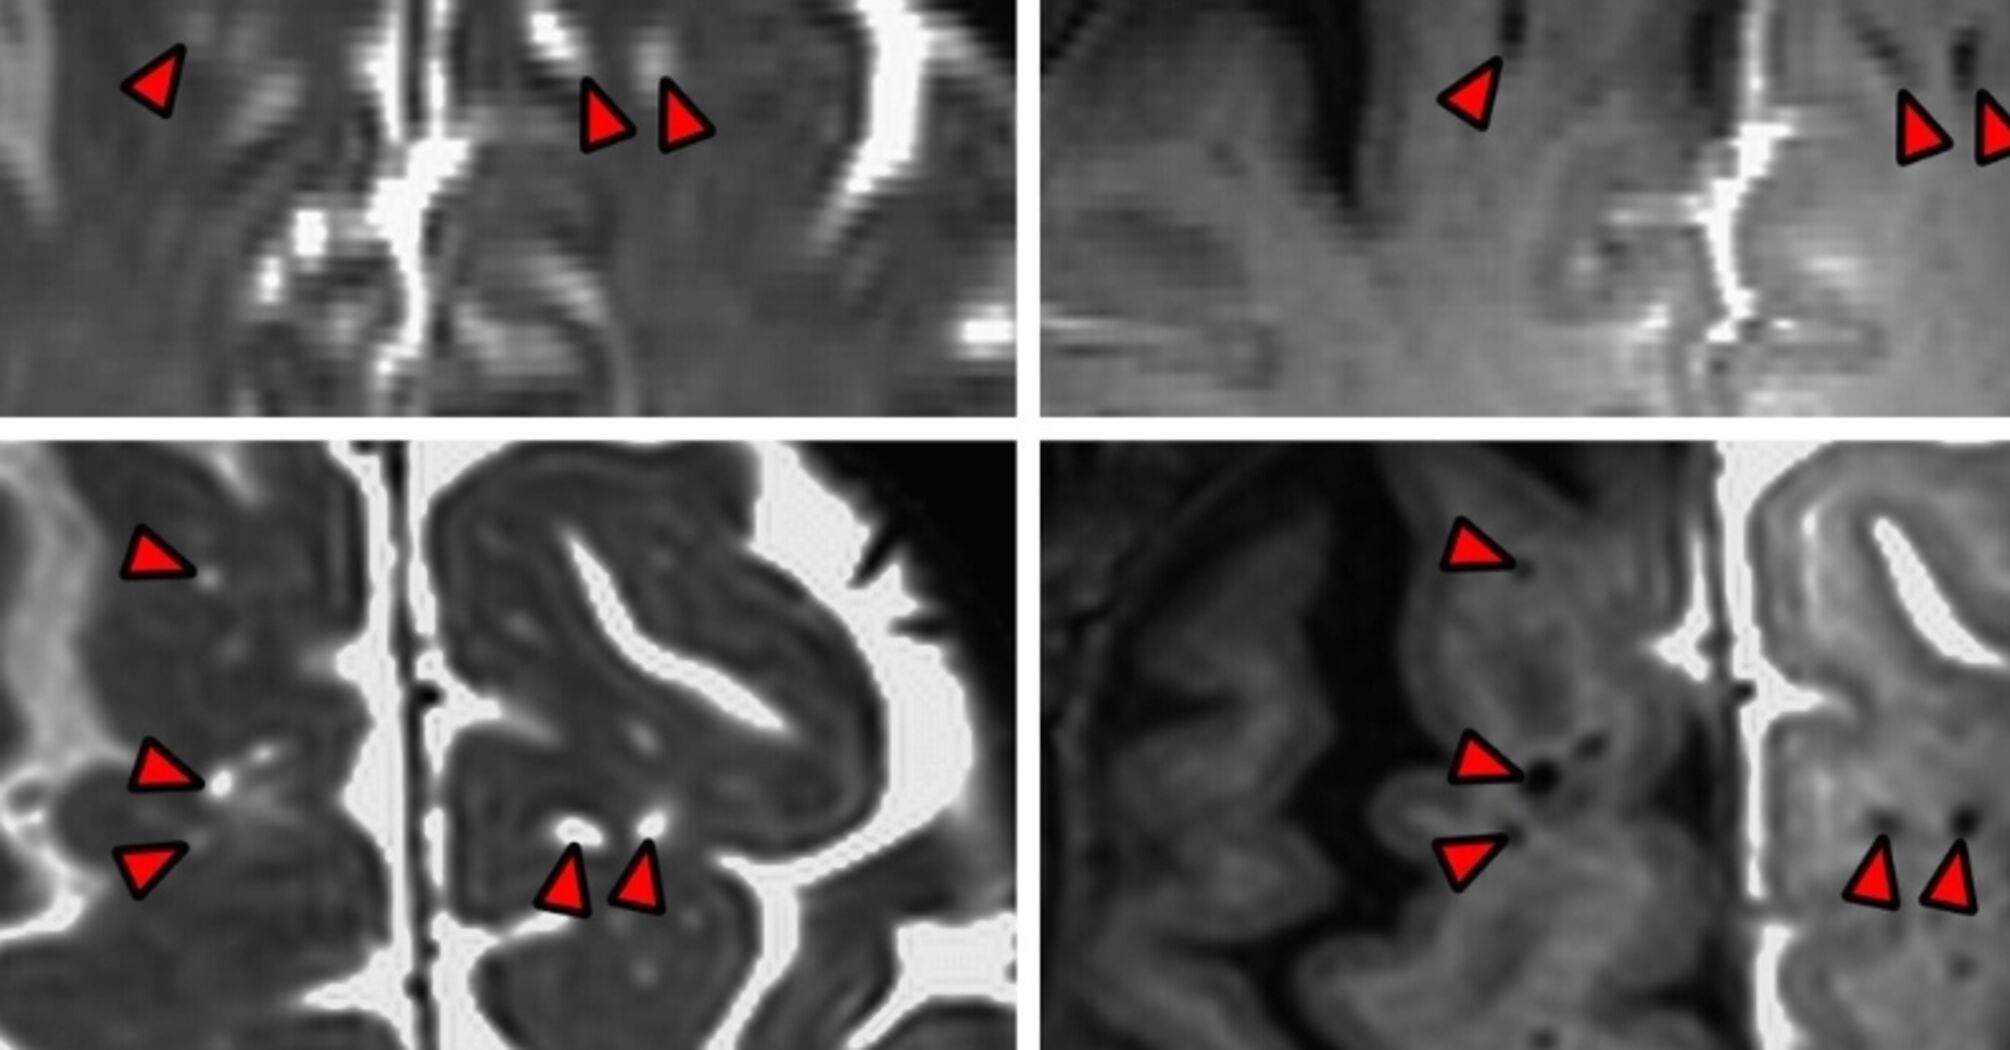

Piantino and his colleagues at OHSU are the first to depict the colorless fluid as it infuses into the brain tissue of a living person.

The study was made possible thanks to the consent of five adults who had undergone brain surgery and needed to have CBF injected for the procedure. So before replacing the fluid, the scientists marked it with a dark contrast marker. Later, a special type of magnetic resonance imaging showed the place where the fluid went into the brains of the study participants.

The findings indicate that the human brain does not absorb cerebrospinal fluid haphazardly, like a sponge. Instead, the fluid penetrates deeper into the neurological tissue and follows the traces of blood vessels.